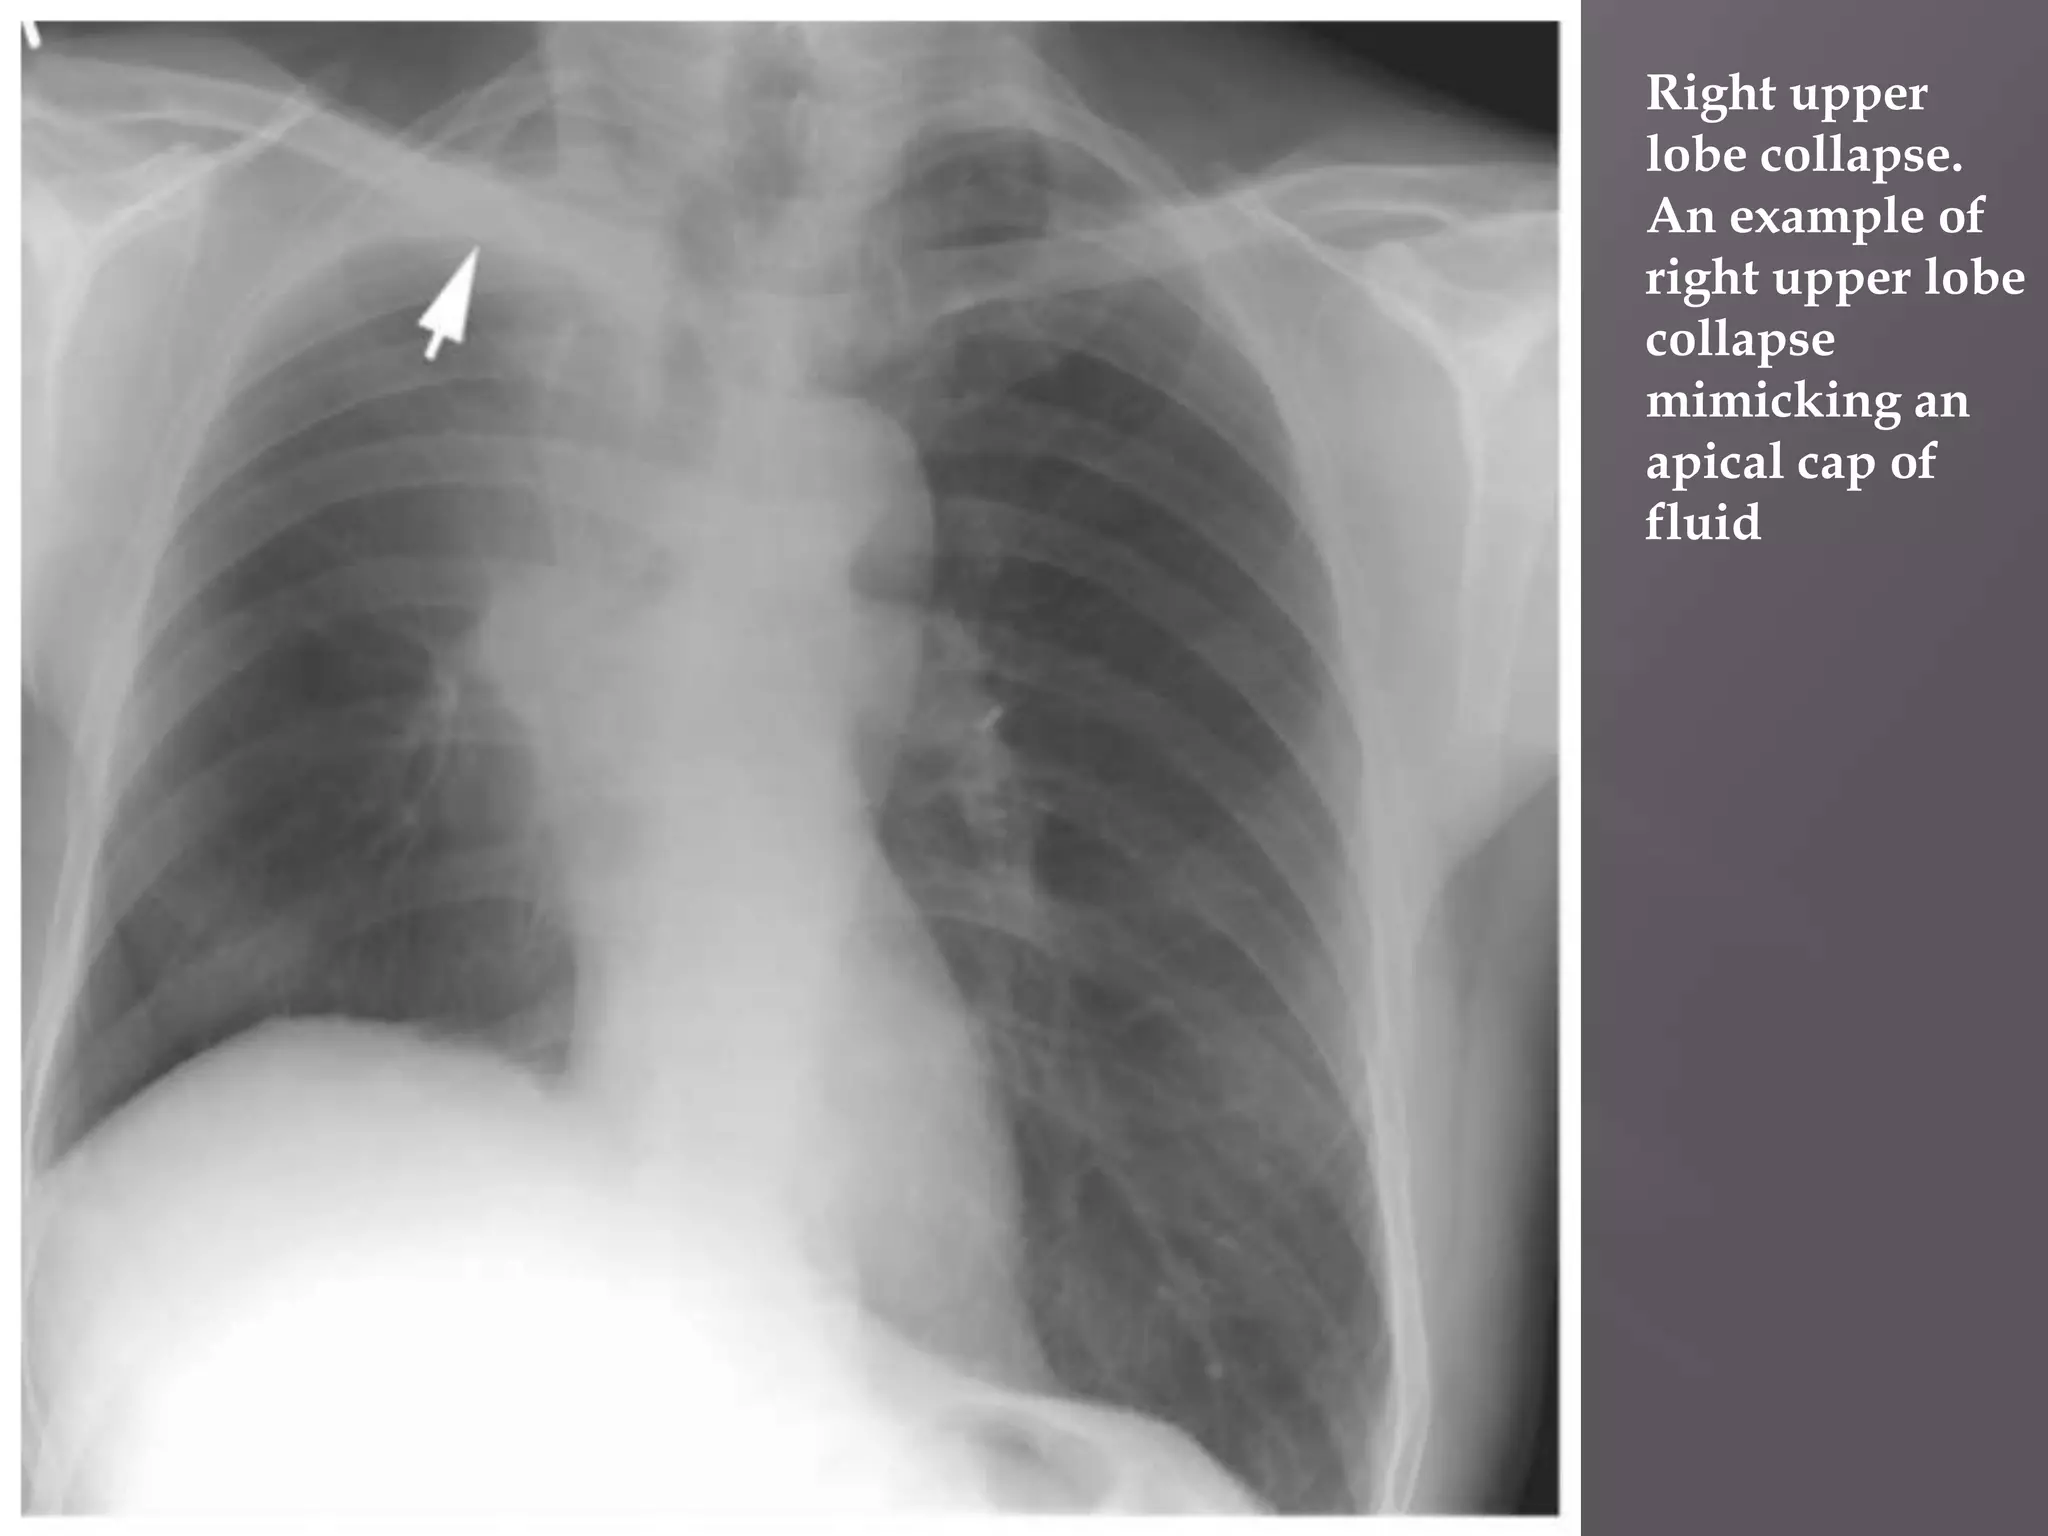

 Right upper

lobe collapse.

An example of

right upper lobe

collapse

mimicking an

apical cap of

fluid

 Right upper lobecollapse. An example of right upper lobe collapse mimicking an apical cap of fluid